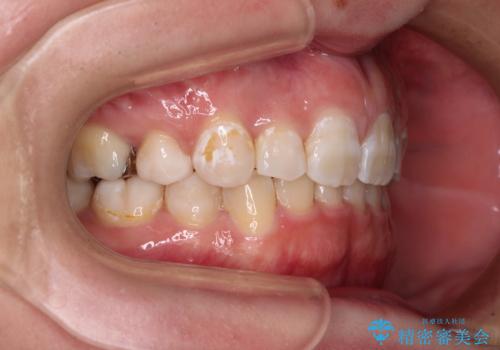

- 八重歯と下顎小臼歯の欠損を気にして来院された患者様です。

下顎小臼歯の欠損により過蓋咬合となっていたため、下顎は臼歯を起こすことで咬み合わせを改善し、八重歯は第一小臼歯2本を抜歯し、補助装置を使用して速やかに改善することとしました。

八重歯は3,4か月で速やかに改善されました。